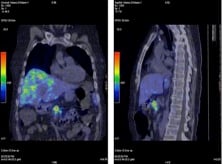

68Ga-DOTA-octreotate-PET (Fig. 7)

68Ga is a generator-produced positron emitter, which has come more and more in to clinical praxis and is also called "the poor mans PET". In several studies it demonstrated higher sensitivity than SRS and can be done in "one-stop" procedure. The better spatial resolution by PET speaks in favour of functional imaging by PET compared with SPECT and planar imaging with SRS.

68Ga-DOTA-octreotate-PET

Peptide receptor radionuclide treatment (PRRT)

Peptide radio-receptor radionuclide therapy with radiolabelled somatostatin analogs is an emerging and convincing treatment modality for patients with unresectable somatostatin receptor positive NETs. The somatostatin receptor is strongly over-expressed in most tumors, resulting in high tumor-to-background ratios. In earlier studies 111Indium-DTPA-octreotide were used at high doses for treatment of GEP-NETs, but the responses to these radioactive compounds were very low. During the last years studies have been performed with 90Yttrium labelled somatostatin analogs and most recently 177Lutetium-DOTA-octreotate. A lot of different studies have been published, unfortunately with different treatment protocols, but in general 25-30% of the patients presented objective responses and up to 40% stabilization of a progressive disease. In general PRRT is regarded as a relatively safe treatment with some haematological and renal toxicity in selected cases. The precise role of PRRT has to be defined in forthcoming randomized clinical trials.